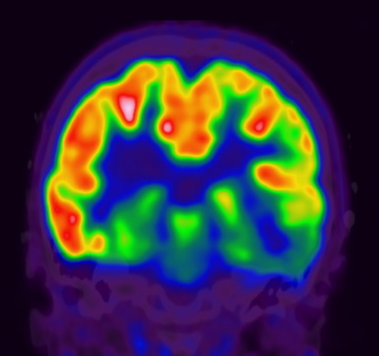

10.2 SPECT Scan

A SPECT scan — single photon emission computed tomography — measures blood flow in the brain. During a seizure, the parts of the brain involved receive a sudden rush of blood. A SPECT scan done during a seizure can capture that rush and pinpoint exactly where it happened.

This is called an ictal SPECT, and it is the most valuable version of the test. It requires careful preparation: a radioactive tracer must be injected within seconds of a seizure beginning, while the seizure is still happening. For this reason, it is only done during an inpatient stay in an epilepsy monitoring unit, where nurses are trained and ready to inject the tracer the moment a seizure starts. The scan is done after the seizure has ended — the tracer stays fixed in the brain tissue for long enough to image it.

The results are then compared to a scan done between seizures (called an interictal SPECT) to identify which area showed the biggest increase in blood flow. The difference between the two scans — often displayed as a color map overlaid on the MRI — highlights the seizure origin zone.

Figure 10.2: Subtraction ictal SPECT (SISCOM) showing increased blood flow in the right frontal lobe during a seizure (bright region, left side of image). The ictal scan is subtracted from the interictal scan and overlaid on the MRI to localize the seizure origin. Adapted from2.